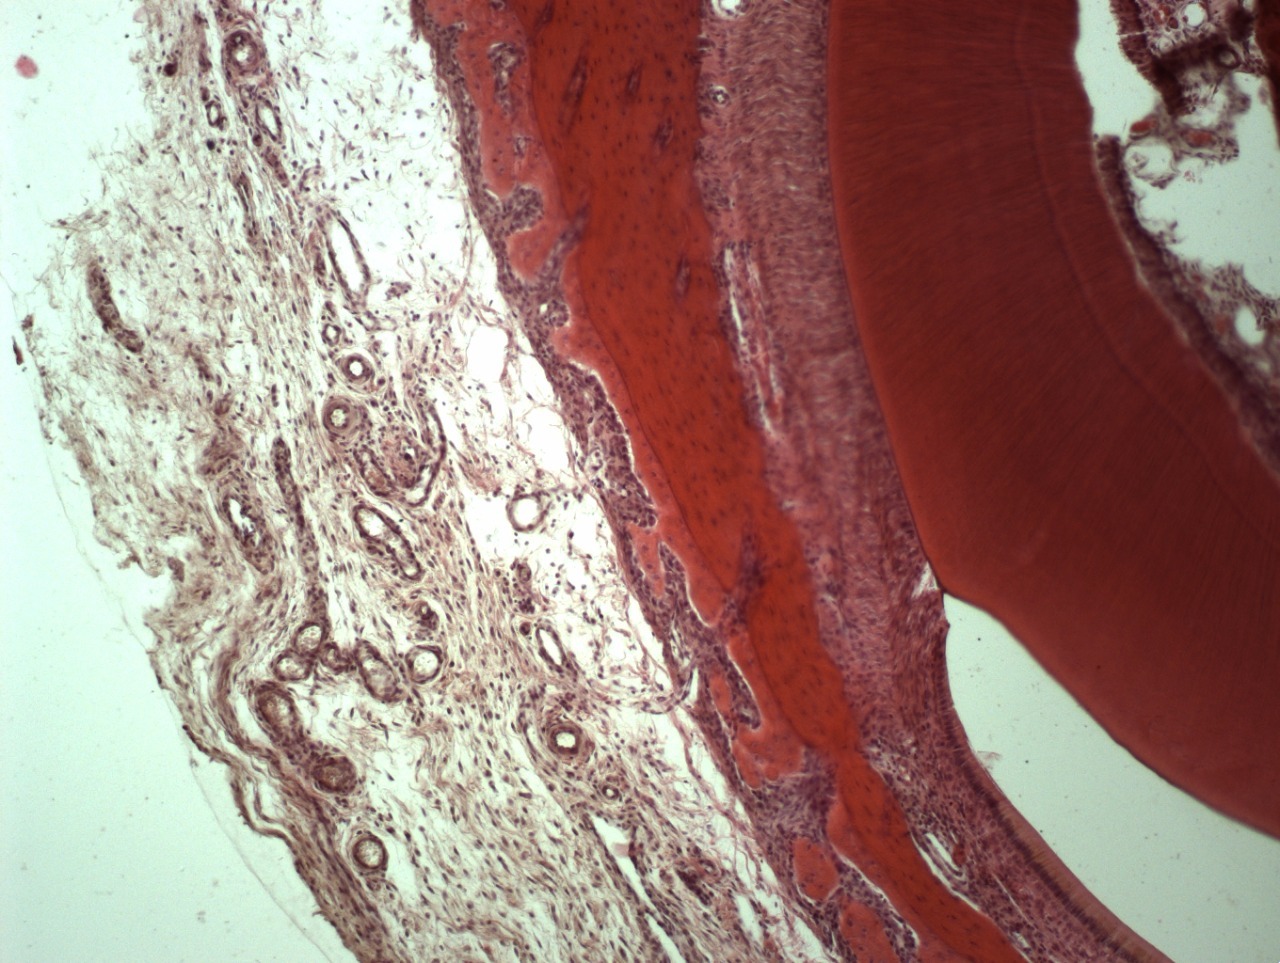

• Все материалы и препараты для стоматологии полностью резорбируются и замещаются собственными тканями на 100%.

• Например, таким образом удаляются все следы жира, белка, нуклеиновых кислот, мертвых клеток и их компонентов, неколлагеновых белков и прочих соединений. Вследствие такой очистки остается только коллагено-минеральный каркас мертвого межклеточного вещества костной ткани, состав которого стабилен на протяжении всей жизни человека.

• Деминерализованную кость применяют дополнительно для восстановления внутренних костных дефектов: через нее лучше растут кровеносные сосуды, так как она содержит морфогенетический белок (МГБ), но за счет отсутствия минерального каркаса не способна удержать трехмерный объем.